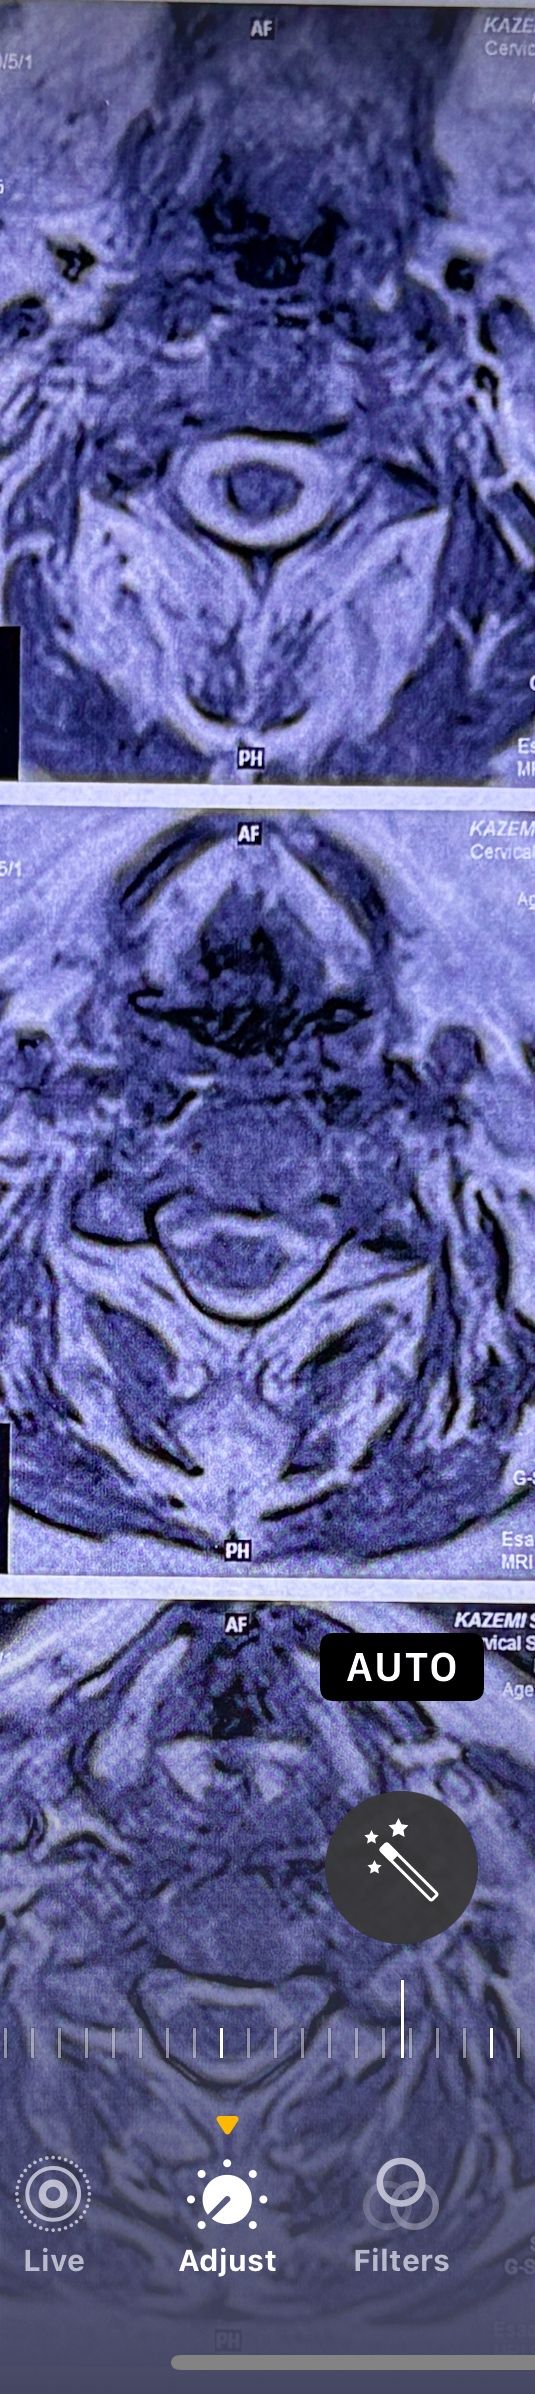

41 years old man presented to my clinic in October 2023 with acute and sever R neck pain with radicular pain to his R upper extremity along C6 dematom since 2 weeks ago. Examination didn’t show any upper motor signs. Was suggested urgent surgery

I ordered EMG/ NCV : showed mild R C6, C7 irritation without any active axonal loss

In his MRI was reported R. para R. IVF Massive extrusion. I decided to control his pain and manage this patient with reevaluation of patient every other session. For 5 sessions i just used acupuncture and laser and IFC and mild adjustments to his R. T3-T7 and mild arthosteem to above and below involved segment. Cervical adjustment considered contraindicated for this patient. From session 6th- 8th i started to use mild/gentle cervical decompression. He used soft cervical collar all the time. His pain decreased by 80 percent

I gave him cervical traction pump to be used 3-5 times per day at home for the next 3 months and i released the patient. He was evaluated every week once for one month and after that every 2 weeks. After 3 month I repeated MRI. Size of the herniated disc was reduced greater than 50 percent. Asked him to do another mri in 6 months

In general: Precise selection of the patients, examination,diagnosis, plan of management, reevaluation and treatment can be done by doctors of chiropractic for the patients with spinal disc herniation and stenosis Moreover giving reasonable time to these kind of patients under direct supervision by their chiropractic doctors can prevent unnecessary surgery. Proper selection of these kind of patients is another important fact that can be done precisely by chiropractors.

MRIs before and after proper management of this patient: